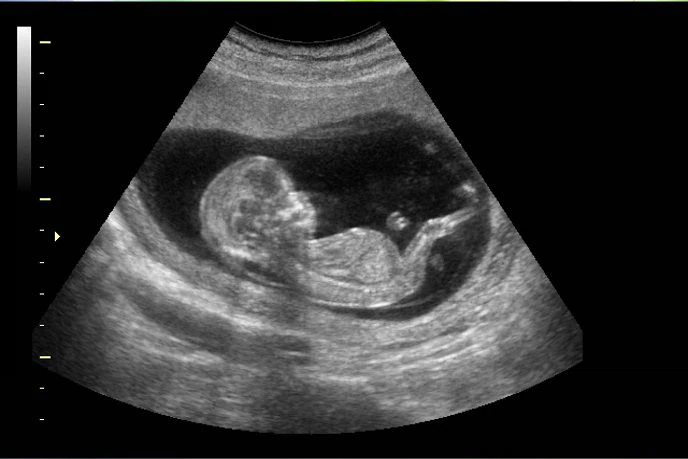

Un estudio apuntó que el Covid-19 aumenta las posibilidades de muerte fetal

Según un estudio realizado por un institución estatal de Estados Unidos el riesgo de muerte fetal es aproximadamente el doble para las mujeres con covid en comparación con las que no lo tienen, y creció hasta cuadriplicarse durante el período en que la variante delta se volvió dominante.

El análisis realizado por los Centros para el Control y la Prevención de Enfermedades (CDC), se basó en más de 1,2 millones de partos ocurridos entre marzo de 2020 y septiembre de 2021.

En general, los casos de mortinatos fueron muy poco frecuentes, sumando 8.154, el 0,65 % del total. Pero, el riesgo de muerte fetal era 1,90 veces más alto en las mujeres contagiadas con covid, resaltó T13.

En ese periodo 1,26 % de los nacimientos fueron un mortinato entre las mujeres con covid, frente a 0,64% para el resto.

Respecto a las no infectadas, el riesgo era 1,47 veces más alto entre las madres positivas para covid antes de la aparición de la variante delta y 4,04 veces más altos luego de que la variante se volvió dominante.